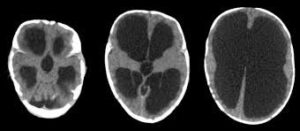

ولفت الى أن الاستسقاء الدماغي هو تراكم السائل الدماغي الشوكي في التجاويف (البطينات) الموجودة في عمق الدماغ مما يؤدي إلى زيادة في حجم هذه البطينات،وبالتالي تحدث ضغطاً على أنسجة الدماغ.

أضاف: يتم تشخيص الاستسقاء الدماغي عن طريق التاريخ المرضي والفحص السريري للمريض،ثم عمل تصوير شعاعي لأنسجة الدماغ بالأشعة المقطعية أو الرنين المغناطيسي، لافتاً الى ان علاج الاستسقاء الماغي هو علاج جراحي إما بزراعة تحويلة لتحويل السائل الماغي الشوكي إلى البطن،أو عن طريق المنظار الجراحي وعمل فتحة صغيرة في قاع البطين الدماغي الثالث.